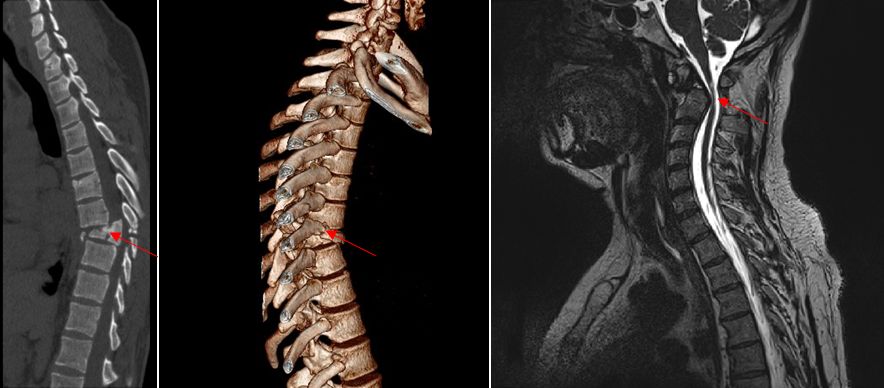

Як результат забою при нейровізуалізації спостерігаються крововиливи (гематомієлія), вогнища розтрощення, набряк, частковий або повний розрив спинного мозку.

КТ та МРТ – це золотий стандарт діагностики при спінальній травмі.